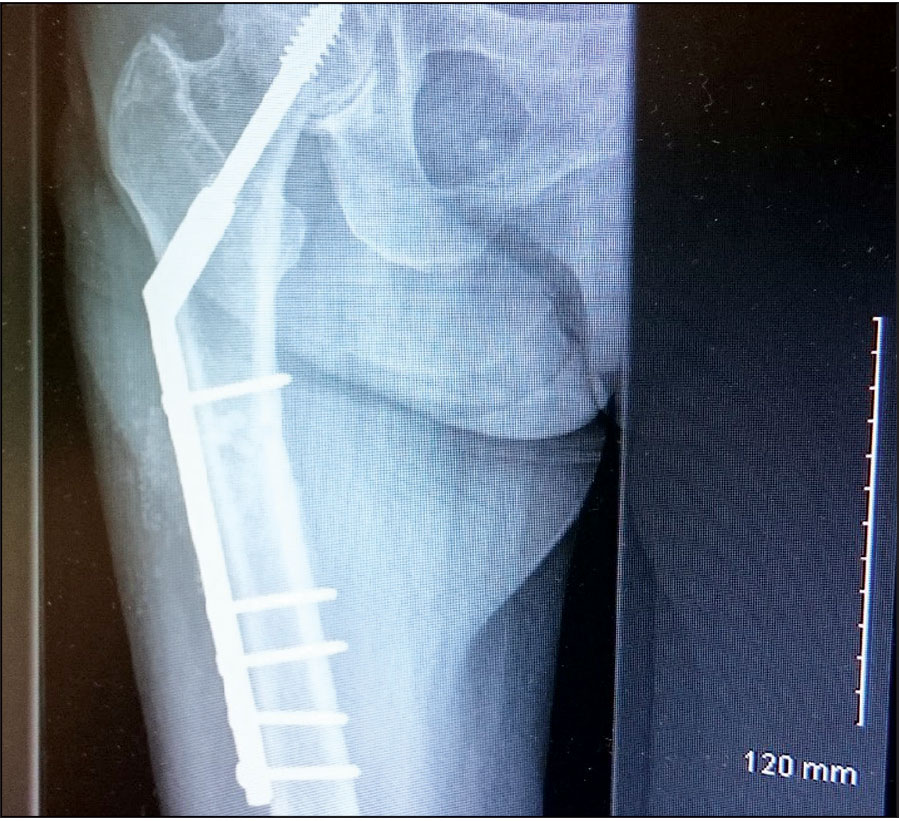

She had an x-ray right femur and pelvis showing an atypical right femur sub-trochanteric fracture. She was taken to the theatre the next day and her two-hole plate was removed without taking the lag screw and was replaced with an eight-hole DHS plate. She was started on physiotherapy and within a few weeks she was walking with a walking frame. She was followed up with regular x-ray. Her alendronate was stopped and she started on teriparatide injections. Teriparatide is a man-made form of the hormone parathyroid which exists naturally in the body.

She was undergoing this treatment when in April 2015 she again had a low energy fall and was brought to hospital with pain right thigh and non-weight bearing. On x-ray she had DHS implant failure. She had the non-union of the original sub trochanteric fracture.